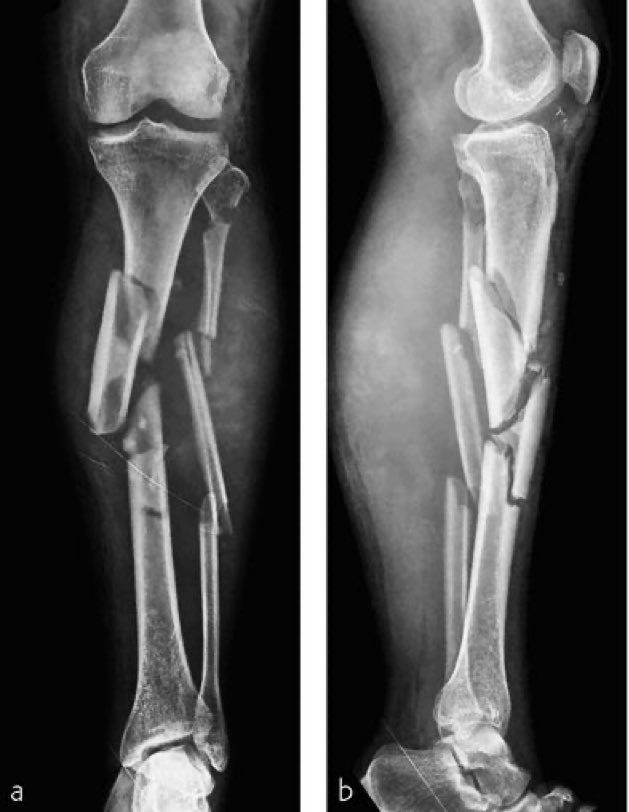

而在此前沃恩晒出的病床照片上,我们能明显看到她的腿被一个巨大的装置固定着,那是跨关节外固定架,这表明了她的伤有多严重。一位医生在社交媒体上晒出了类似需要固定架的胫骨骨折x光片(这并不是沃恩的腿部x光),给大家科普这大概是怎样的伤情。